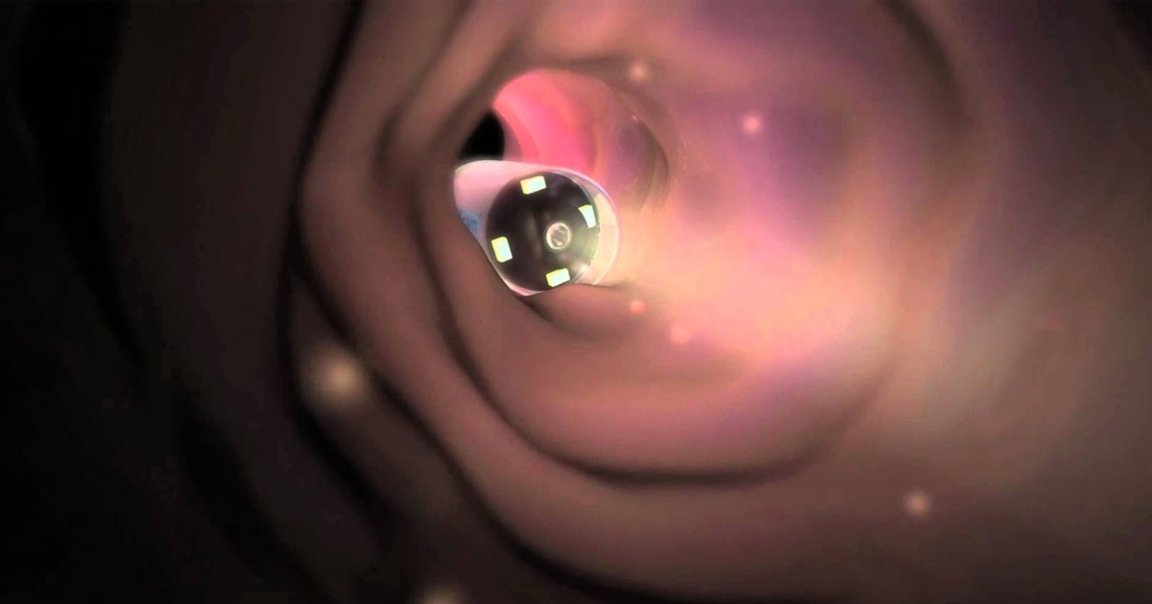

The capsules, called PillCams, are easily swallowed and are far less invasive than other cancer screening methods, according to the researchers behind the capsule. The cameras inside each pill can take two pictures per second as they travel through the entire digestive system. The images are stored in a data recorder that the patient carries around with them.

Swallowing the camera is also a lot less uncomfortable than traditional endoscopy, which involves sending a long flexible tube down the patient’s throat and into the esophagus.